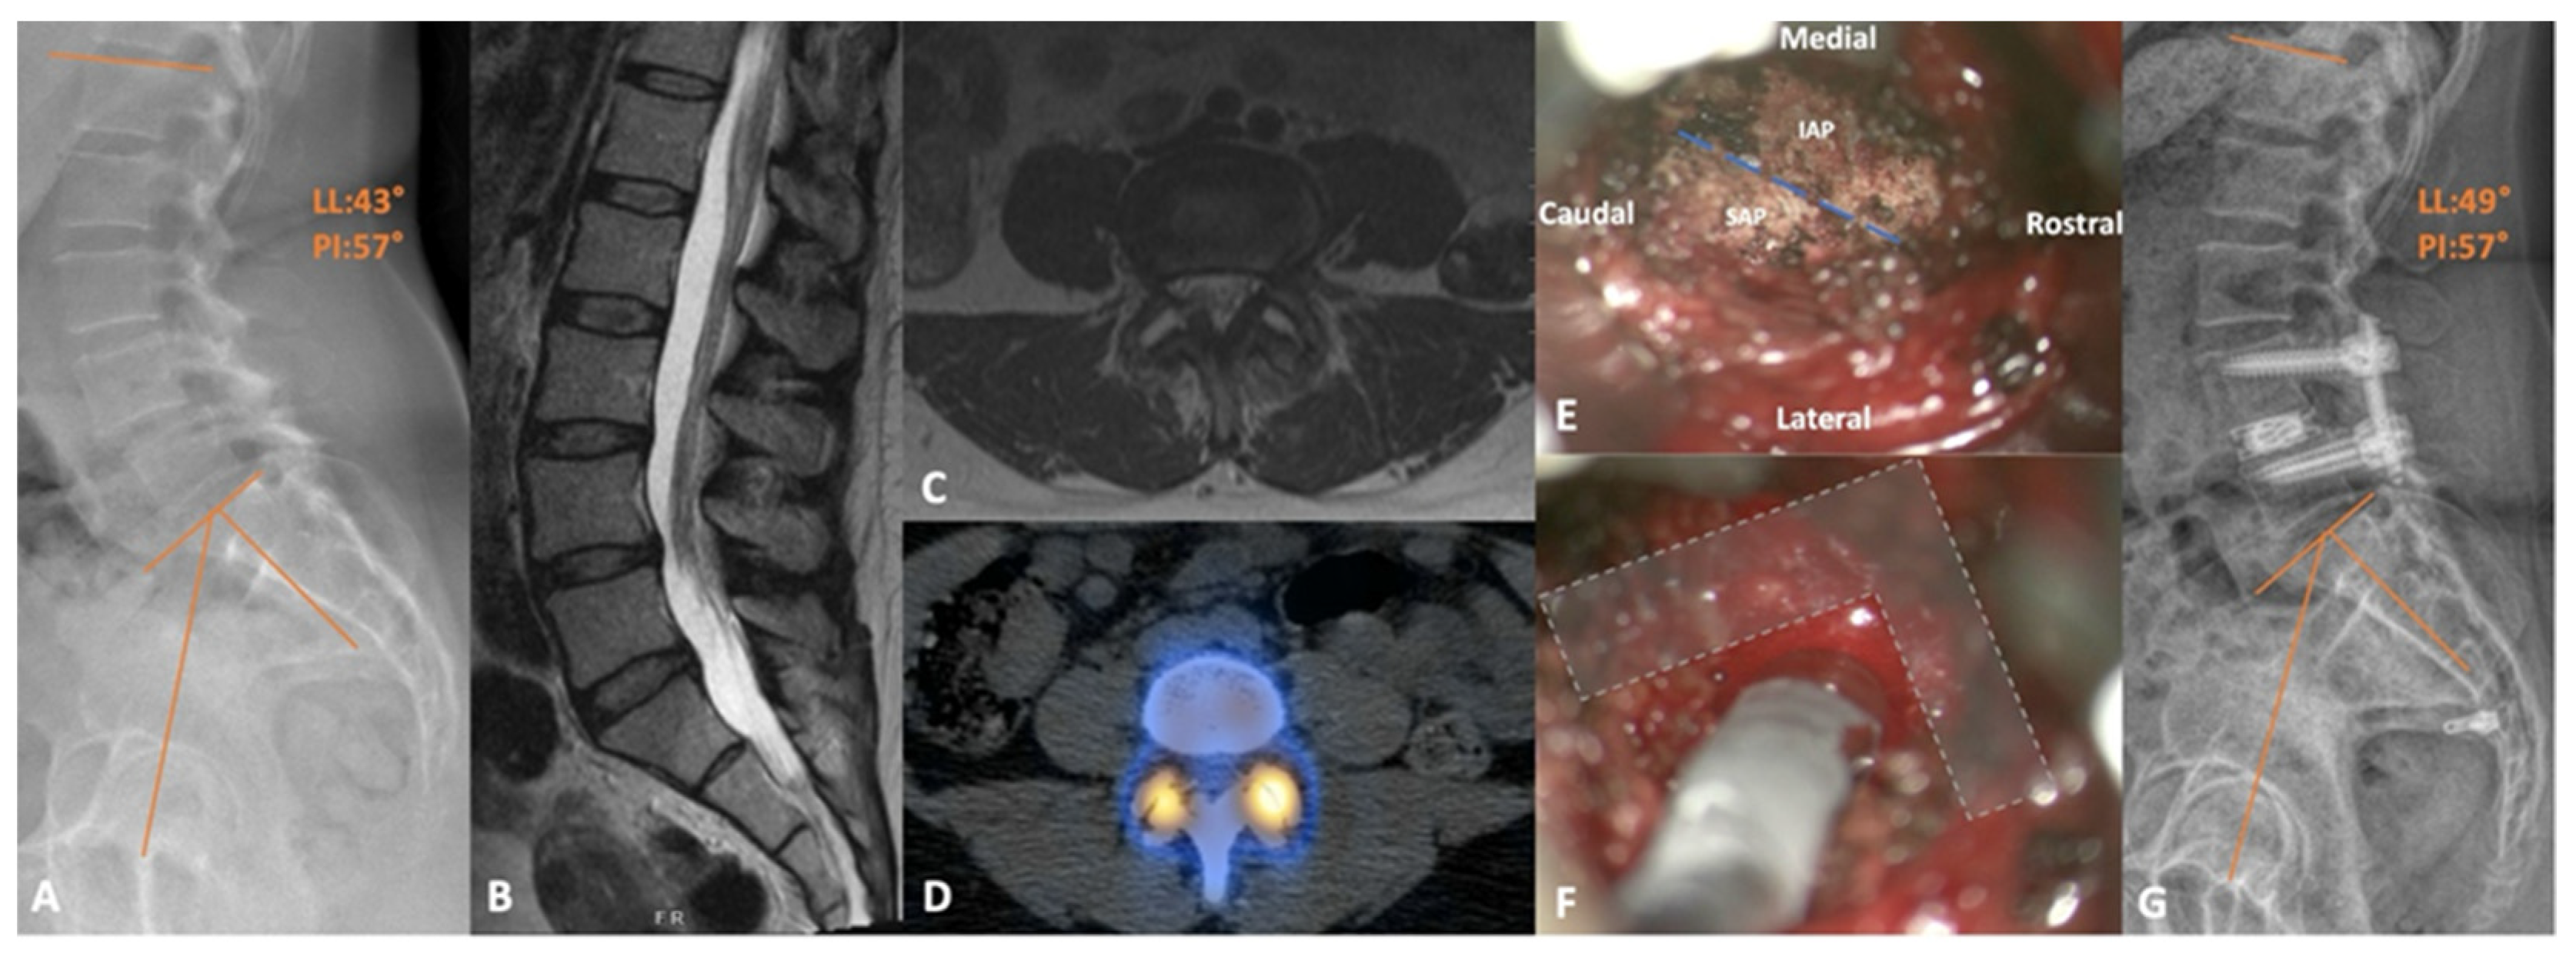

6. Transfacet Lumbar Interbody Fusion

Outcomes

- Khalifeh, J.M.; Dibble, C.F.; Stecher, P.; Dorward, I.; Hawasli, A.H.; Ray, W.Z. Transfacet Minimally Invasive Transforaminal Lumbar Interbody Fusion With an Expandable Interbody Device—Part I: 2-Dimensional Operative Video and Technical Report. Oper. Neurosurg. 2020, 19, E473–E479. [Google Scholar] [CrossRef] [PubMed]

- Khalifeh, J.M.; Dibble, C.F.; Stecher, P.; Dorward, I.; Hawasli, A.H.; Ray, W.Z. Transfacet Minimally Invasive Transforaminal Lumbar Interbody Fusion With an Expandable Interbody Device—Part II: Consecutive Case Series. Oper. Neurosurg. 2020, 19, 518–529. [Google Scholar] [CrossRef] [PubMed]